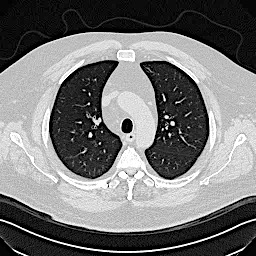

Denoising diffusion probabilistic models (DDPMs) have achieved unprecedented success in computer vision. However, they remain underutilized in medical imaging, a field crucial for disease diagnosis and treatment planning. This is primarily due to the high computational cost associated with (1) the use of large number of time steps (e.g., 1,000) in diffusion processes and (2) the increased dimensionality of medical images, which are often 3D or 4D. Training a diffusion model on medical images typically takes days to weeks, while sampling each image volume takes minutes to hours. To address this challenge, we introduce Fast-DDPM, a simple yet effective approach capable of improving training speed, sampling speed, and generation quality simultaneously. Unlike DDPM, which trains the image denoiser across 1,000 time steps, Fast-DDPM trains and samples using only 10 time steps. The key to our method lies in aligning the training and sampling procedures. We introduced two efficient noise schedulers with 10 time steps: one with uniform time step sampling and another with non-uniform sampling. We evaluated Fast-DDPM across three medical image-to-image generation tasks: multi-image super-resolution, image denoising, and image-to-image translation. Fast-DDPM outperformed DDPM and current state-of-the-art methods based on convolutional networks and generative adversarial networks in all tasks. Additionally, Fast-DDPM reduced training time by a factor of 5 and sampling time by a factor of 100 compared to DDPM. Our code is publicly available at: https://github.com/mirthAI/Fast-DDPM.